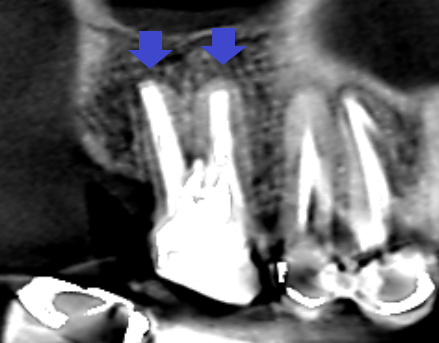

精密根管治療6カ月後の経過観察時の冠状断のCT画像です。青い矢印の先にあった未治療だった根管が根の先まで根管充填されています。赤い矢印の先にあった膿の影が消失し歯槽骨が再生しています。

精密根管治療6カ月後の経過観察時の冠状断のCT画像です。青い矢印の先にあったパーフォレーションによる膿の影が消失しています。